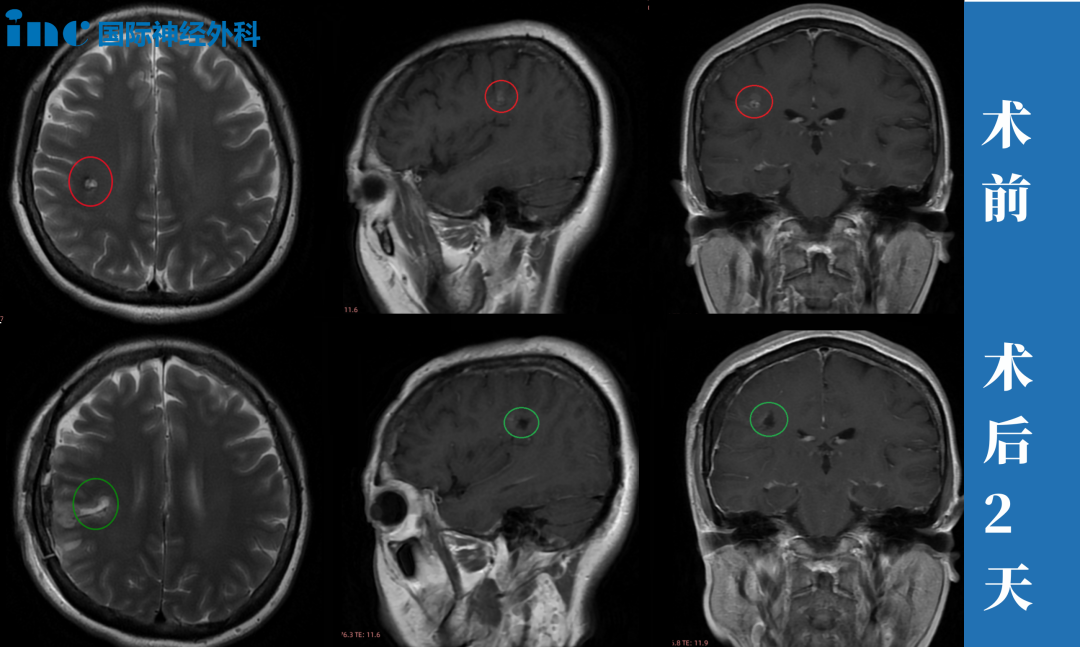

简要病史:23岁的彦文一年前感觉右手无力,写不了字,5月份就医检查左半卵圆中心海绵状血管瘤,住院治疗一周,期间右腿、右脚无力,走路不利索,医院给予保守治疗后出院。彦文父母一直苦苦寻求能为年轻的孩子顺利手术的主刀医生。今年4月,他们看到了国际神外教授巴教授来华示范手术消息,于是奔赴苏州寻求教授为孩子主刀手术。

治疗过程:4月9日,在苏州独墅湖医院,巴教授已经顺利为彦文顺利完成手术,全切左半卵圆中心海绵状血管瘤。

术后情况:术后一周,已经可以自行下床活动,术后的右手麻木等症状有所缓解,术后两周多顺利出院,目前术后两个月,可以正常行走骑自行车,基本恢复正常生活。

简要病史:47岁的邓女士事业如日中天,对于工作,有着较强的责任心及较高的自我要求。一次定期体检却发现右脑额叶深部占位,大小约8mm,医生判断是海绵状血管瘤。咨询了上海的专家,但是医生的解释让他害怕,不建议手术,因为病灶部位太深,靠近功能区,手术风险大。而且目前病灶体积小,建议每年复查随访。查出海绵状血管瘤之后,邓女士发现有时工作太累了会头疼,近期还出现 6~7次无预兆性突然出现眼前漂浮物的现象,很快自行缓解。

治疗过程:2024年3月28日,巴教授中国行期间,一场疑难功能区海绵状血管瘤示范手术,成功拯救了47岁的邓女士于病魔的阴影之中。“I believe you, it’s a very (我很信任您,这是一个)就是正确的选择。”术后2小时,麻醉刚清醒,47岁的邓女士激动地用英语说出自己的术后感受,重新露出了大大的笑脸。

术后情况:手术1天,顺利出ICU,转入普通病房,交流顺畅、肢体活动正常,恢复良好。“我的手有力量,Thank you very much!”此时的邓女士回归了往日的健谈、声音洪亮、神采奕奕。术后2天,邓女士表示已经可以自主下床活动,“已经可以走来走去”,巴教授查房用中文为邓女士点赞。